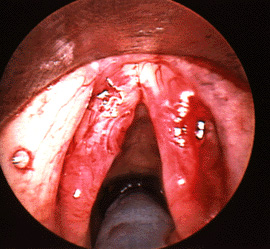

Dark image of vocal cyst

The image to the the right shows bilateral cysts on vocal folds that may have developed at the site of previous nodules. The cyst on the right is more solid in appearance but did contain fluid. The cyst on the left has a little dark red dot showing where there has been bleeding into the cyst.